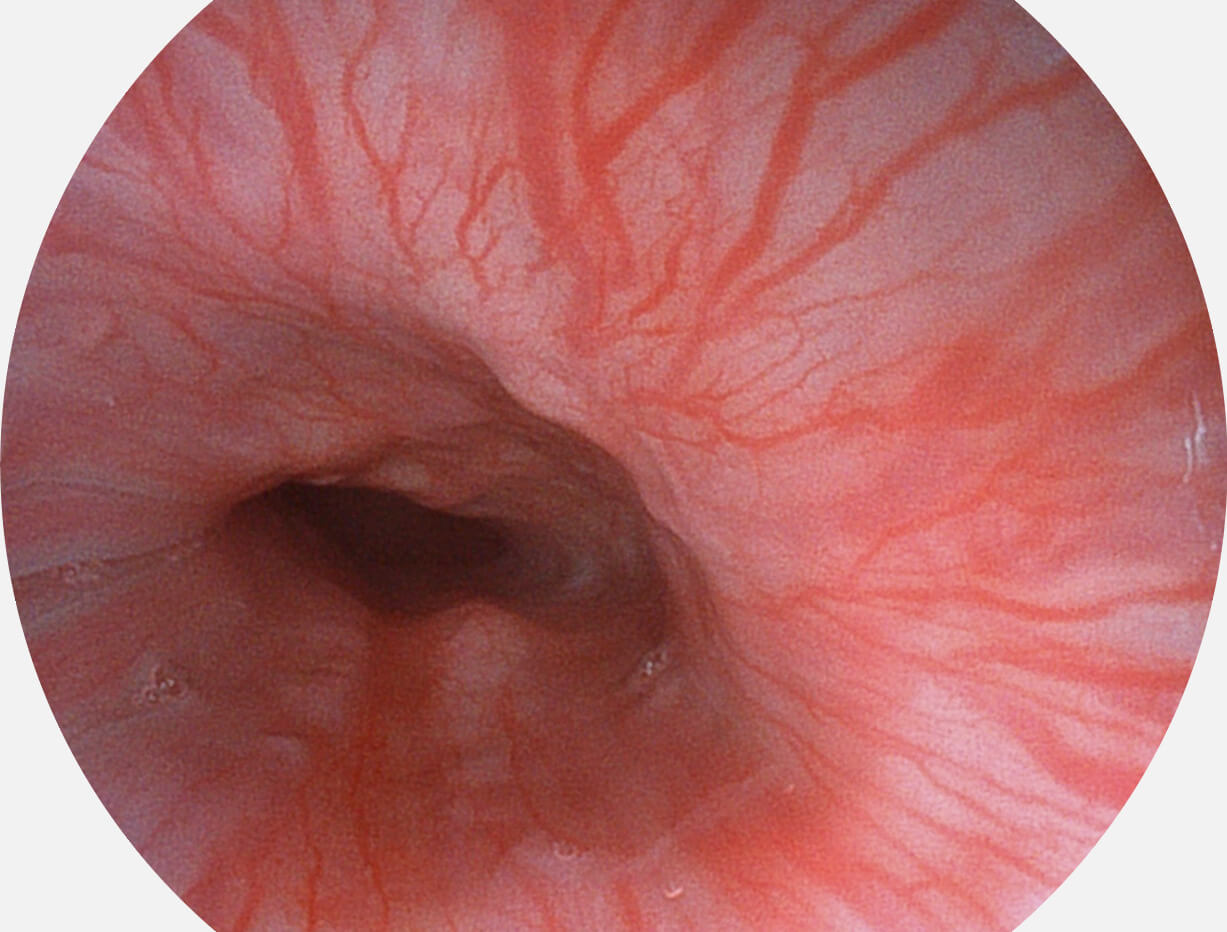

强调浅层黏膜结构的同时,保证照明亮度和提升浅层微血管与中层血管颜色对比度,病变边界更清晰。

白光图像

VIST图像